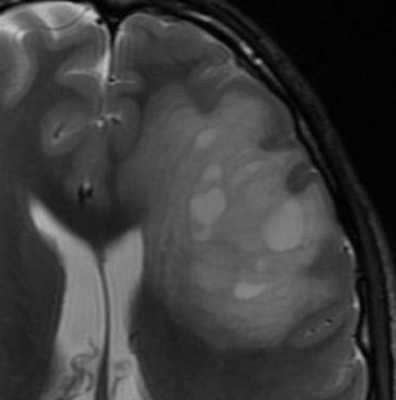

К редким агрессивным формам рассеянного склероза относится опухолевидный тип Марбурга и концентрический тип Бало. Бляшки достигают больших размеров с отеком и “слоистостью” в связи с частыми обострениями. Агрессивные варианты яркие на МРТ типа ДВИ и хорошо контрастируются.

МРТ головного мозга. Т2-взвешенная аксиальная МРТ. Рассеянный склероз, Концентрический тип Бало.